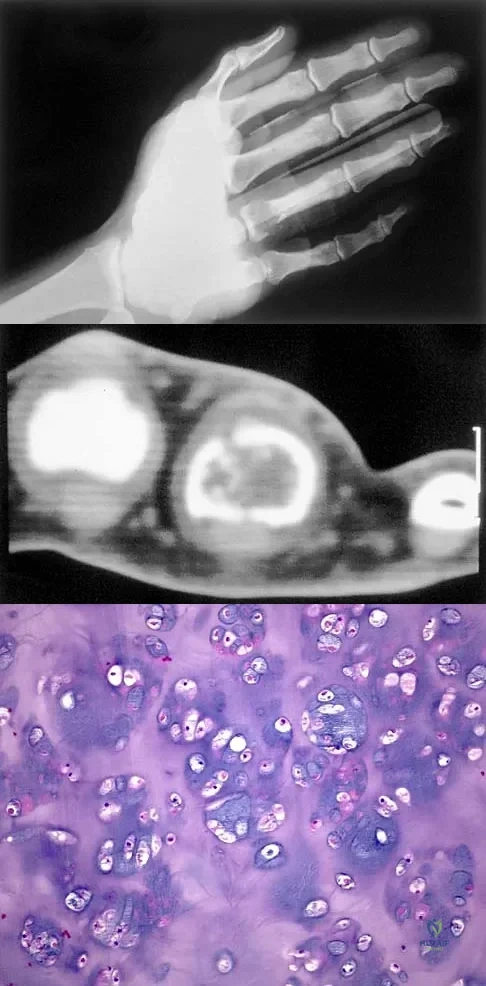

Question 40

A 30-year-old woman has pain in her right hand. The radiograph, CT scan, and biopsy specimen are seen in Figures 38a through 38c. What is the most likely diagnosis?

Explanation